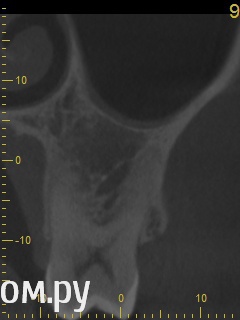

Анатолий М Опубликовано 21 апреля, 2014 Поделиться Опубликовано 21 апреля, 2014 Добрый день. Помогите пожалуйста.17 зуб (верхняя семерка с права). Пол года назад был депульпирован. Все это время присутствуют боли под этим зубом по симптомам очень похожие на кисту (распирание, боль ноющая не сильная, то появляется то сама собой изчезает. при перкуссии 17 зуб слегка болезненный). 2 месяца наза решили зуб перелечить. На ОПТГ ситуация до перелечивания. По снимку видно что первоначальное лечение было проведено плохо. Корни были плохо пройдены и плохо заполены цементом.Месяц хождения с гидроокисью кальция на воде никакого эфекта не дали. Врачи считают что под зубом есть киста. И предлагают удалить зуб. Так как перелечивание не помогло.Прилагаю снимок КЛКТ после лечения. Зуб все еще под временной пломбой. Из трех врачей лишь один разгледел на КЛКТ кисту под 17 зубом. Два других ни на КЛКТ ни на прицельных никакой кисты не видят. Направили к неврологу. Думают что киста если она и есть (в чем они не уверены) не дает имеющихся симптомов.Пожалуйста посмотрите на КЛКТ. Есть ли там киста или нет? И могут ли боли быть от нее?Заранее спасибо. Ссылка на комментарий

Анатолий М Опубликовано 21 апреля, 2014 Автор Поделиться Опубликовано 21 апреля, 2014 Снимок во время лечения делали? Коффердам и оптика использовались? На кт в тех срезах что Вы выложили кисты не вижу Снимки во время лечения делали три раза прицельные с иголками в каналах. Но они остались у врача. У меня их нет. Но она по ним кисты не видела. Коффердам использовали только при первом посещении когда вскрывали старую пломбу и прорабатывали каналы. При последующих посещениях при смене лекарст его не использовали так как кольцо на зубе плохо держалось и постоянно слетало. Плюс травмировало десну.Микроскоп использовали все три раза. По словам врача (врач высшей категории эндодонтист зав отделением):При вскрытии старой пломбы каналы практически не заполены цементирующим составом. Иструмент при вскрытии пломбы в каналы проваливался. Хотя стояла постоянна пломба. Из трех каналов лишь один был проработан до верхушки корня. Два других либо до половины либо на треть. Врачь полностью прошла все каналы и даже залезла за апекс. туда при первом пломбировании врач даже не пыталась лезть. При третьем посещении врач констатировала что каналы чистые. Никаких признаков инфекции нет. И белезненная перкуссия от чего то другого. Специально проводила ревизию каналов при втором и третьем посещении без анастезии что бы понять где болит. Но так и не поняла. Повела на консультацию к профессору в их стоматологи. Посмотрев контрольную КТ он сказал что там киста и надо удалять зуб! Похоже что мой врач с ним не очень согласна, хотя и спорить не стала поэтому отправила меня на консультацию к неврологу. Ниже срезы конрольного КТ после месяца лечения гидрооксидом кальция на воде. Срезы по дуге. Сделал как смог. Шаг срезов как я понимаю 1мм. Линия по перек дуги снимок номер 1 (см нумерацию в конце названия файла) Ссылка на комментарий

ромашечка Опубликовано 21 апреля, 2014 Поделиться Опубликовано 21 апреля, 2014 (изменено) Месяц хождения с гидроокисью кальция на воде никакого эфекта не дали. Зуб все еще под временной пломбой В каналах всё ещё гидроокись?? даже залезла за апекс?? Зачем? При третьем посещении врач констатировала что каналы чистые. Никаких признаков инфекции нет. И белезненная перкуссия от чего то другого. Специально проводила ревизию каналов при втором и третьем посещении без анастезии что бы понять где болит. Может у меня пробелы какие- но я не понимаю такой тактики. Болезненная перкуссия вполне может быть от того что каналы пустые или временно запломбированнны. Но мой взгляд , дотаточно качественно запломбировать ПОСТОЯННО каналы и проблема должна исчезнуть. Кисты не вижу. Изменено 21 апреля, 2014 пользователем ромашечка 1 Ссылка на комментарий

Анатолий М Опубликовано 22 апреля, 2014 Автор Поделиться Опубликовано 22 апреля, 2014 В каналах все еще гидроокись. Я просил врача поставить постоянную пломбу еще 3 недели назад и оставить зуб в покое. Но она говорит что боится закрывать зуб так как думает что там и вправду может быть киста. Хотя сама ее на снимках не видит. То что там есть киста мнение одного из 3 врачей которые смотрели меня в кресле и КТ во всех возможных срезах. Два остальных включая моего врача ничего подозрительного не видят. Врачь сказала ходи пока с временной пломбой. Проконсультируйся с неврологом. И если невролог потвердит что проблема стоматологиечская то 17 зуб кандидат на удаление. Вариант с депофорезом она впринципе не рассматривает.В любом случае всем спасибо за консультацию. Думаю что никакой кисты там и вправду нет. Попробую попасть к неврологу. А дальше будет видно. Ссылка на комментарий